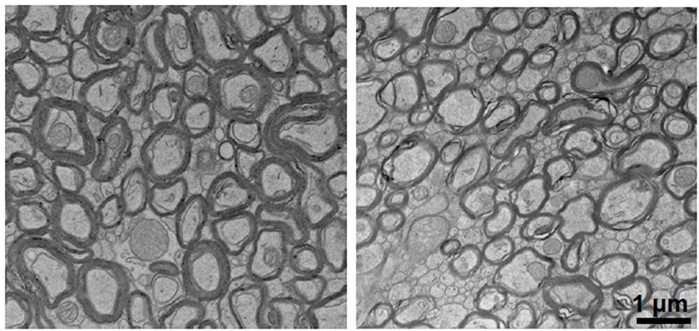

In Alzheimer’s mouse models, depleted lithium dramatically accelerated the formation of amyloid-beta plaques and structures that resemble neurofibrillary tangles. Lithium depletion also activated inflammatory cells in the brain called microglia, impairing their ability to degrade amyloid; caused the loss of synapses, axons, and neuron-protecting myelin; and accelerated cognitive decline and memory loss — all hallmarks of Alzheimer’s disease.

Lithium deficiency thinned the myelin that coats neurons (right) compared to normal mice (left). Images: Yankner Lab